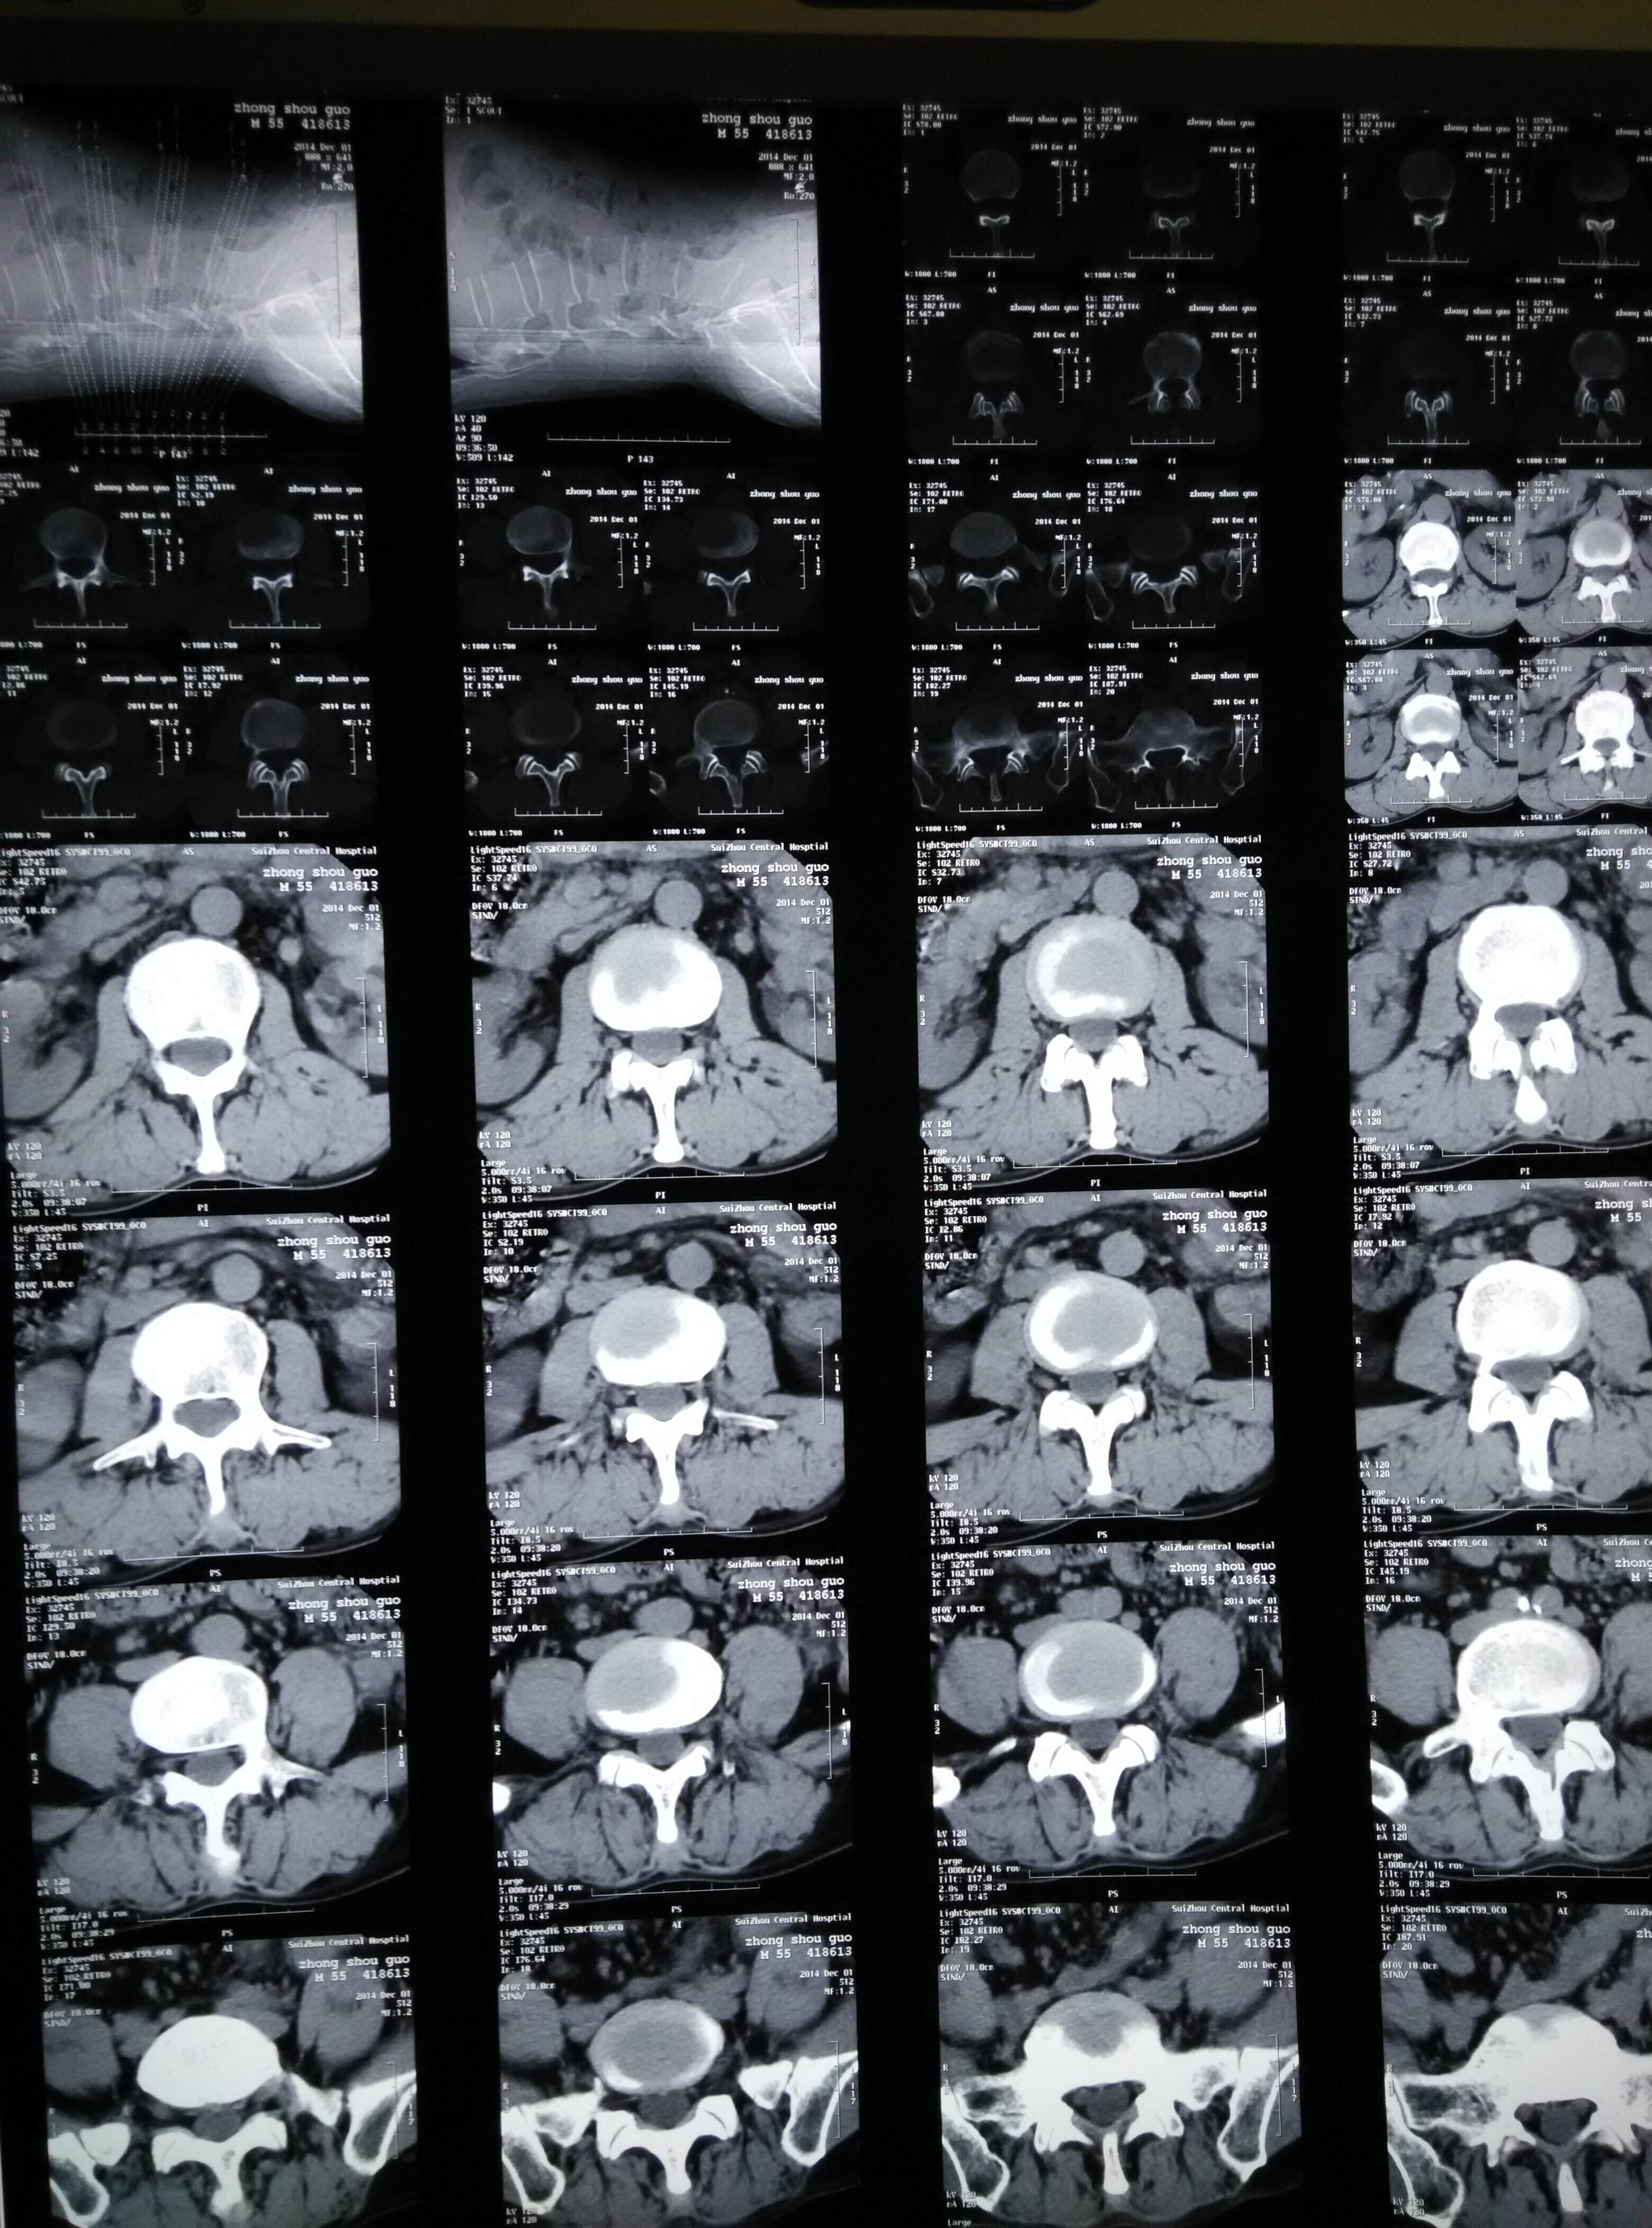

腰椎CT片示:腰2-5椎体骨质增生,腰4/5、腰5/骶1椎间盘突出。如图(1)示:

诊断:腰椎间盘突出症